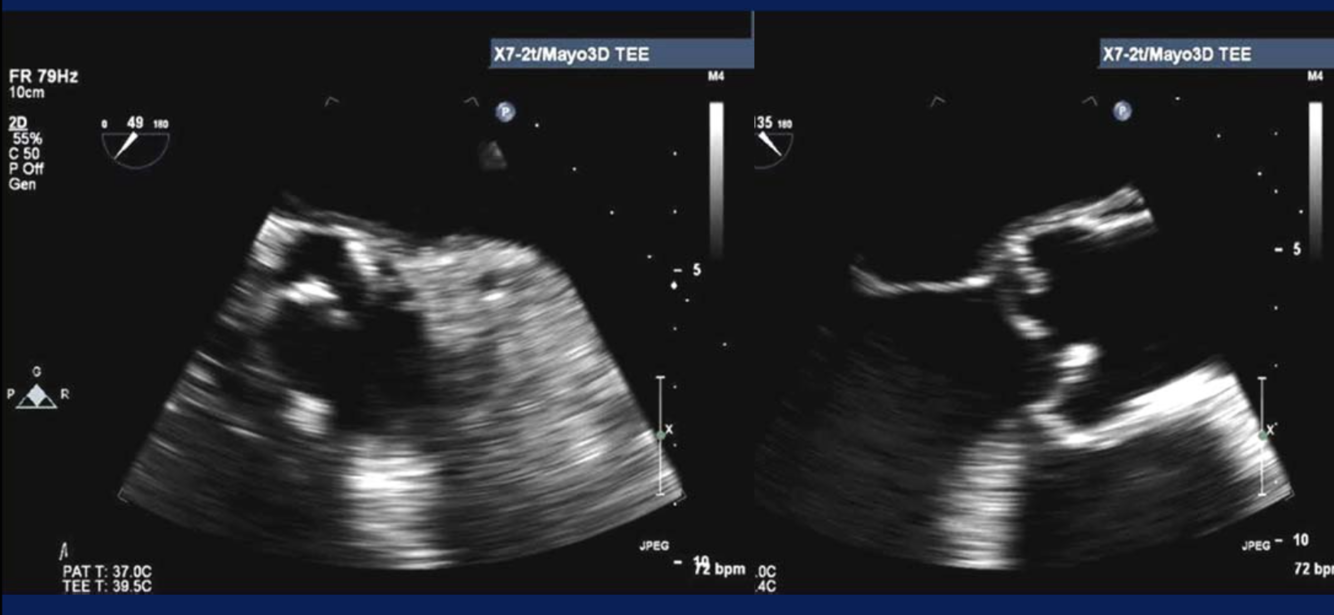

Diagnosis?

Perforated MV leaflet (*clue is to see the PISA off the midline)